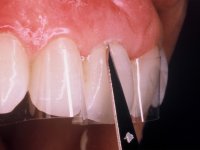

After the impression of the implant using a double-mix technique with double viscosity and the collection of shape and color information by the ceramist, we proceed with the work. In the model, a syn octa was placed over the implant, and a screw was placed on it to assess its emergence in relation to the incisal edge. Then, an adequate emergence profile in the artificial gingiva was prepared. A abutment with characteristics suitable for overbite and simultaneously capable of receiving a veneer was waxed on top of this scenario. This waxing gave rise to the manual milling of a very personalized abutment. An infrastructure in Zr was also made for the veneer with a very great adaptation to the abutment. On this infrastructure ceramics were placed. Ceramic fluorescence sought to compensate for the lack of fluorescence that Zr had and obviously further customize the aesthetics. The adhesive bridge was removed and the definitive work was placed. The syn octa was initially tightened with 35 N to the implant and then the Zr abutment was tightened over the syn octa with 15 N. The access hole was plugged and then the veneer was cemented with resin-reinforced glass ionomer. After 15 years, the patient returned to the consultation with tooth mobility. Fortunately, nowadays we have the possibility of having dynamic tightening wrenches that allow tightening screws with greater inclinations. An access cavity was made without damaging the incisal edge of the veneer. Tightening was done with a dynamic wrench with 15 N torque. The hole was covered with Teflon and filled with composite resin. This solution allowed the problem to be solved in a simple and economical way.